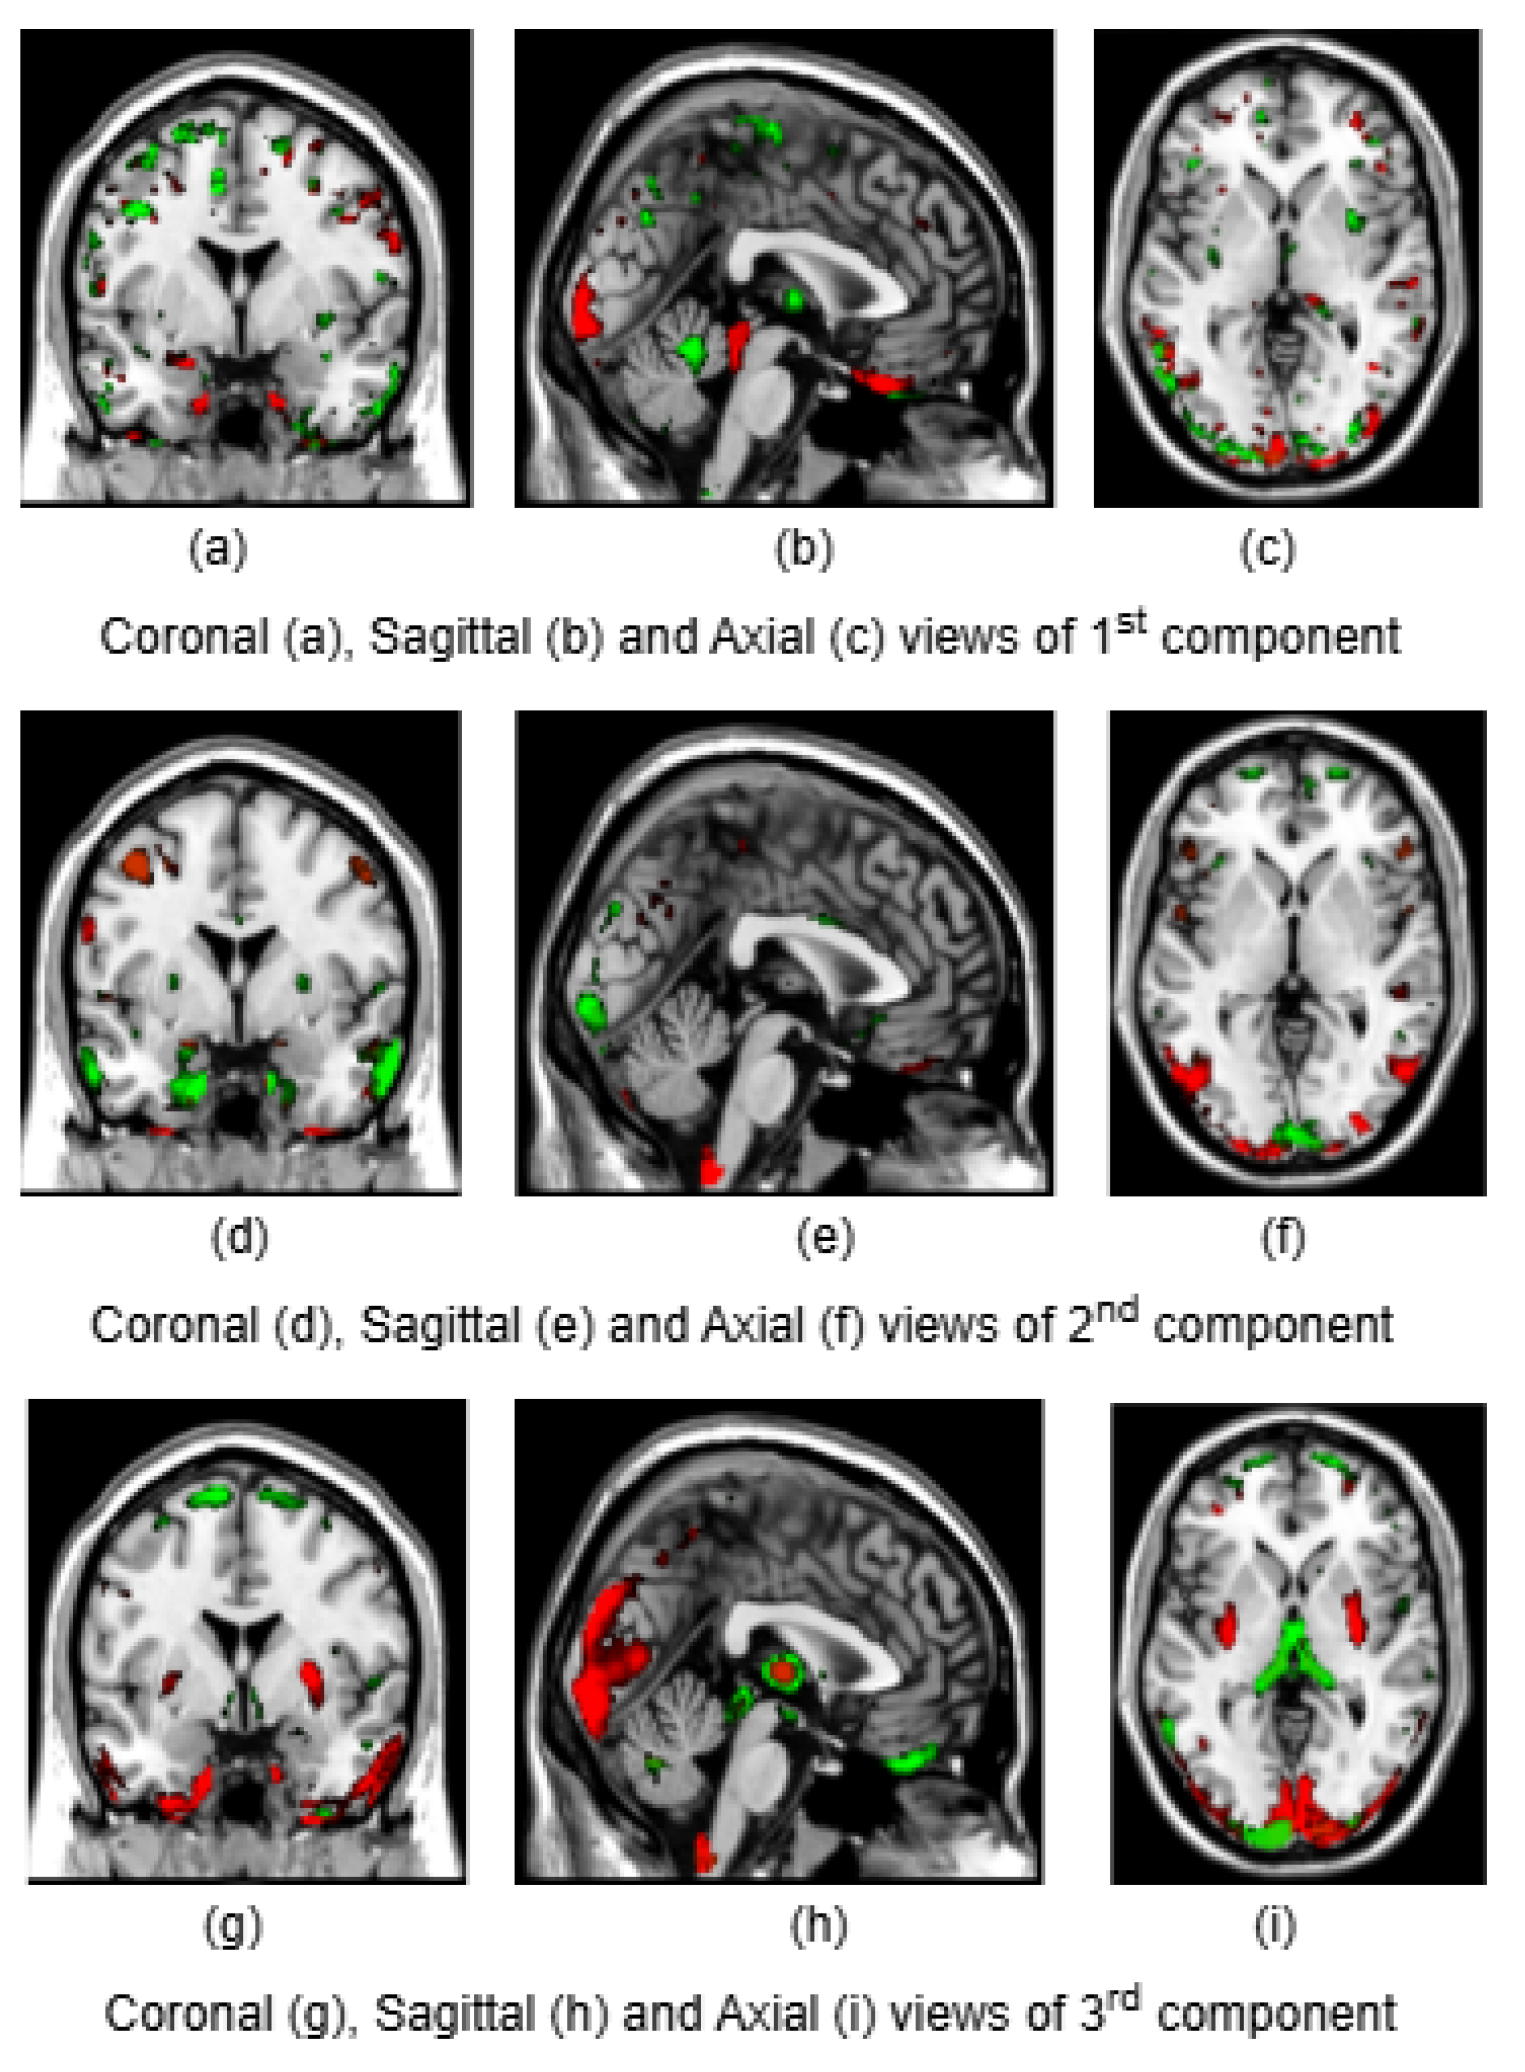

To illustrate the brain regions, the top PCs of the first three significantly correlated GM and FA components were plotted for both CCA and DCCAE results. To plot the brain regions, the CCA/DCCAE components were traced back to PCA components using the weight matrix of CCA/DCCAE, and the top PCA components were then mapped to the brain regions.

Figure 1 and Figure 2 depict GM and FA regions for CCA respectively, while Figure 3 and Figure 4 portray GM and FA regions for DCCAE respectively, with green indicating positively correlated GM and FA regions and red indicating negatively correlated regions. The GM regions identified by the first component of CCA include the middle temporal gyrus, precentral gyrus, middle frontal gyrus, superior frontal gyrus, and sub-gyral regions. The second component highlights the cuneus, middle occipital gyrus, superior frontal gyrus, lingual gyrus, and superior temporal gyrus. The third component encompasses the superior frontal gyrus, middle frontal gyrus, cuneus, superior temporal gyrus, middle occipital gyrus, and thalamus. Similarly, the first component of DCCAE reveals cuneus, middle temporal gyrus, precentral gyrus, middle frontal gyrus, rectal gyrus, superior temporal gyrus, inferior parietal lobule, middle frontal gyrus and superior frontal gyrus. The second component identifies cuneus, middle occipital gyrus, superior frontal gyrus, middle frontal gyrus, sub-gyral, postcentral gyrus, precuneus and middle temporal gyrus. The third component includes middle temporal gyrus, precentral gyrus, cuneus, lingual gyrus, middle occipital gyrus, inferior frontal gyrus, postcentral gyrus and inferior parietal lobule.

Figure 1. Coronal, sagittal and axial views of first, second, and third components of GM identified by CCA

When examining the direct similarity between components of CCA and DCCAE, we found out that most of the CCA components (for both GM and FA ) have high and significant correlations (shown in Tables 3 and 4) with some of the DCCAE components. For example, CCA GM component 1 is significantly and negatively correlated to DCCAE GM components 1 and 2, and positively correlated to DCCAE GM component 3. Similar results were observed for FA components where CCA FA component 1 was linked to DCCAE FA components 1 and 2 negatively and component 3 positively. The negative correlation observed in Tables 3 and 4 does not indicate a fundamental contradiction in the relationship between GM and FA features. Instead, it suggests that for the same brain region, CCA encodes a change in one direction (increase or decrease), while DCCAE encodes it in the opposite direction. However, the underlying GM-FA association remains consistent across both models. This difference in sign can be further illustrated in Figure 1 and 3, where the first components from CCA and DCCAE show similar spatial patterns, particularly in the posterior occipital region but the color representation differs indicating an increase in one model and a decrease in the other.

We also examined the contributing brain regions of components that shared the same brain regions. The top PCs of the CCA and DCCAE components highlighted common regions for GM and FA. The first CCA component correlates with the first, second and third DCCAE components. The brain regions of the first CCA components which include middle temporal gyrus, precentral gyrus, middle frontal gyrus, superior temporal gyrus and sub-gyral while DCCAE’s first component identified middle temporal gyrus, middle frontal gyrus, and sub-gyrus, DCCAE’s second component identified middle temporal gyrus and middle forntal gyrus, DCCAE’s third component identified superior temporal gyrus and precentral gyrus. Similarly, common FA regions were also observed for CCA FA component and DCCAE FA components. The brain regions of the first CCA components include corticospinal tract, anterior thalamic radiation and forceps minor, and DCCAE’s first, second and third components identified the brain regions pointed by the first component of CCA.